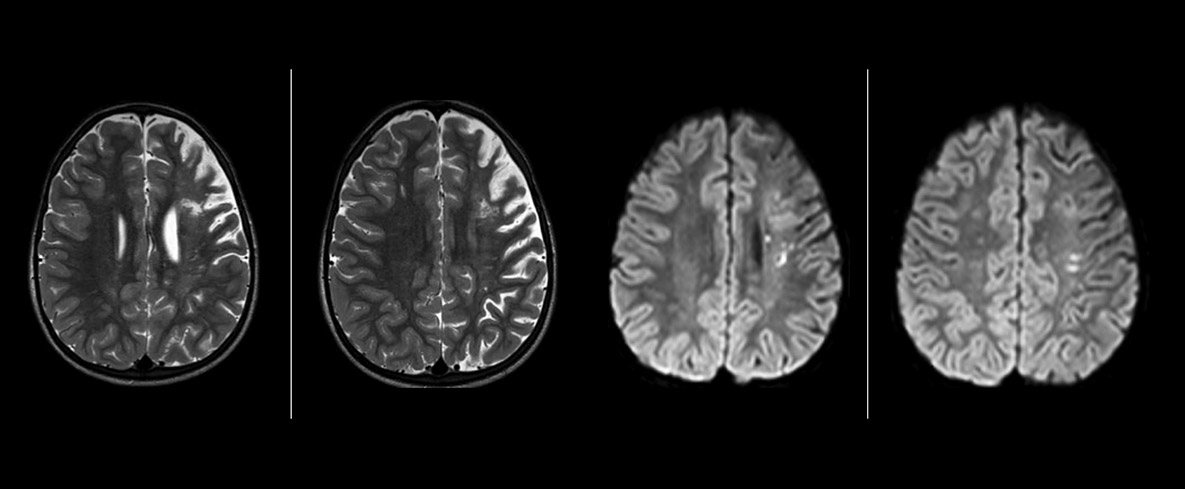

The value of susceptibility weighted imaging in visualizing brain injury is well documented. The Philips multi-echo SWIp technique provides fast susceptibility weighted imaging with enhanced susceptibility contrast and high resolution.

“SWIp helps us identify blood or blood products, calcification, and diseases that affect the vascular system,” says Dr. Miller. “In children with traumatic brain injuries, it highlights areas that are injured, better than some of the previous techniques that we were using. These children often have micro-injuries that cause small amounts of blood or tissue damage. Adding SWIp helps us to better characterize the extent and nature of the injury. Having characterized an injury to the extent of what’s possible supports our diagnostic confidence.”

Full adoption after initial comparison

“I would definitely recommend other users to implement SWIp. We initially added the SWIp sequence following a lot of support for its utility in the literature. Then we directly compared SWIp to the 2D gradient echo sequences that we were using. After a good amount of clinical experience in seeing its benefits, we were confident to replace the old sequences with SWIp. It gives us a better assessment of the physiological processes of the brain that were less apparent on our previous imaging sequences,” says Dr. Miller. “SWIp is now a routine sequence for imaging traumatic brain injury patients at PCH, and it’s episodically added for patients who have intracranial vascular abnormalities.”

“I believe SWIp is rapidly becoming the standard in imaging traumatic brain injury, because of its high sensitivity to venous blood products. SWIp may even help attract patients; our neurosurgeons often ask to have the patients imaged on our scanners with highly sensitive techniques like SWIp. There’s also a growing application of SWI sequences in other vascular abnormalities because of the possibilities around physiological assessment of the brain than just a standard structural imaging.”